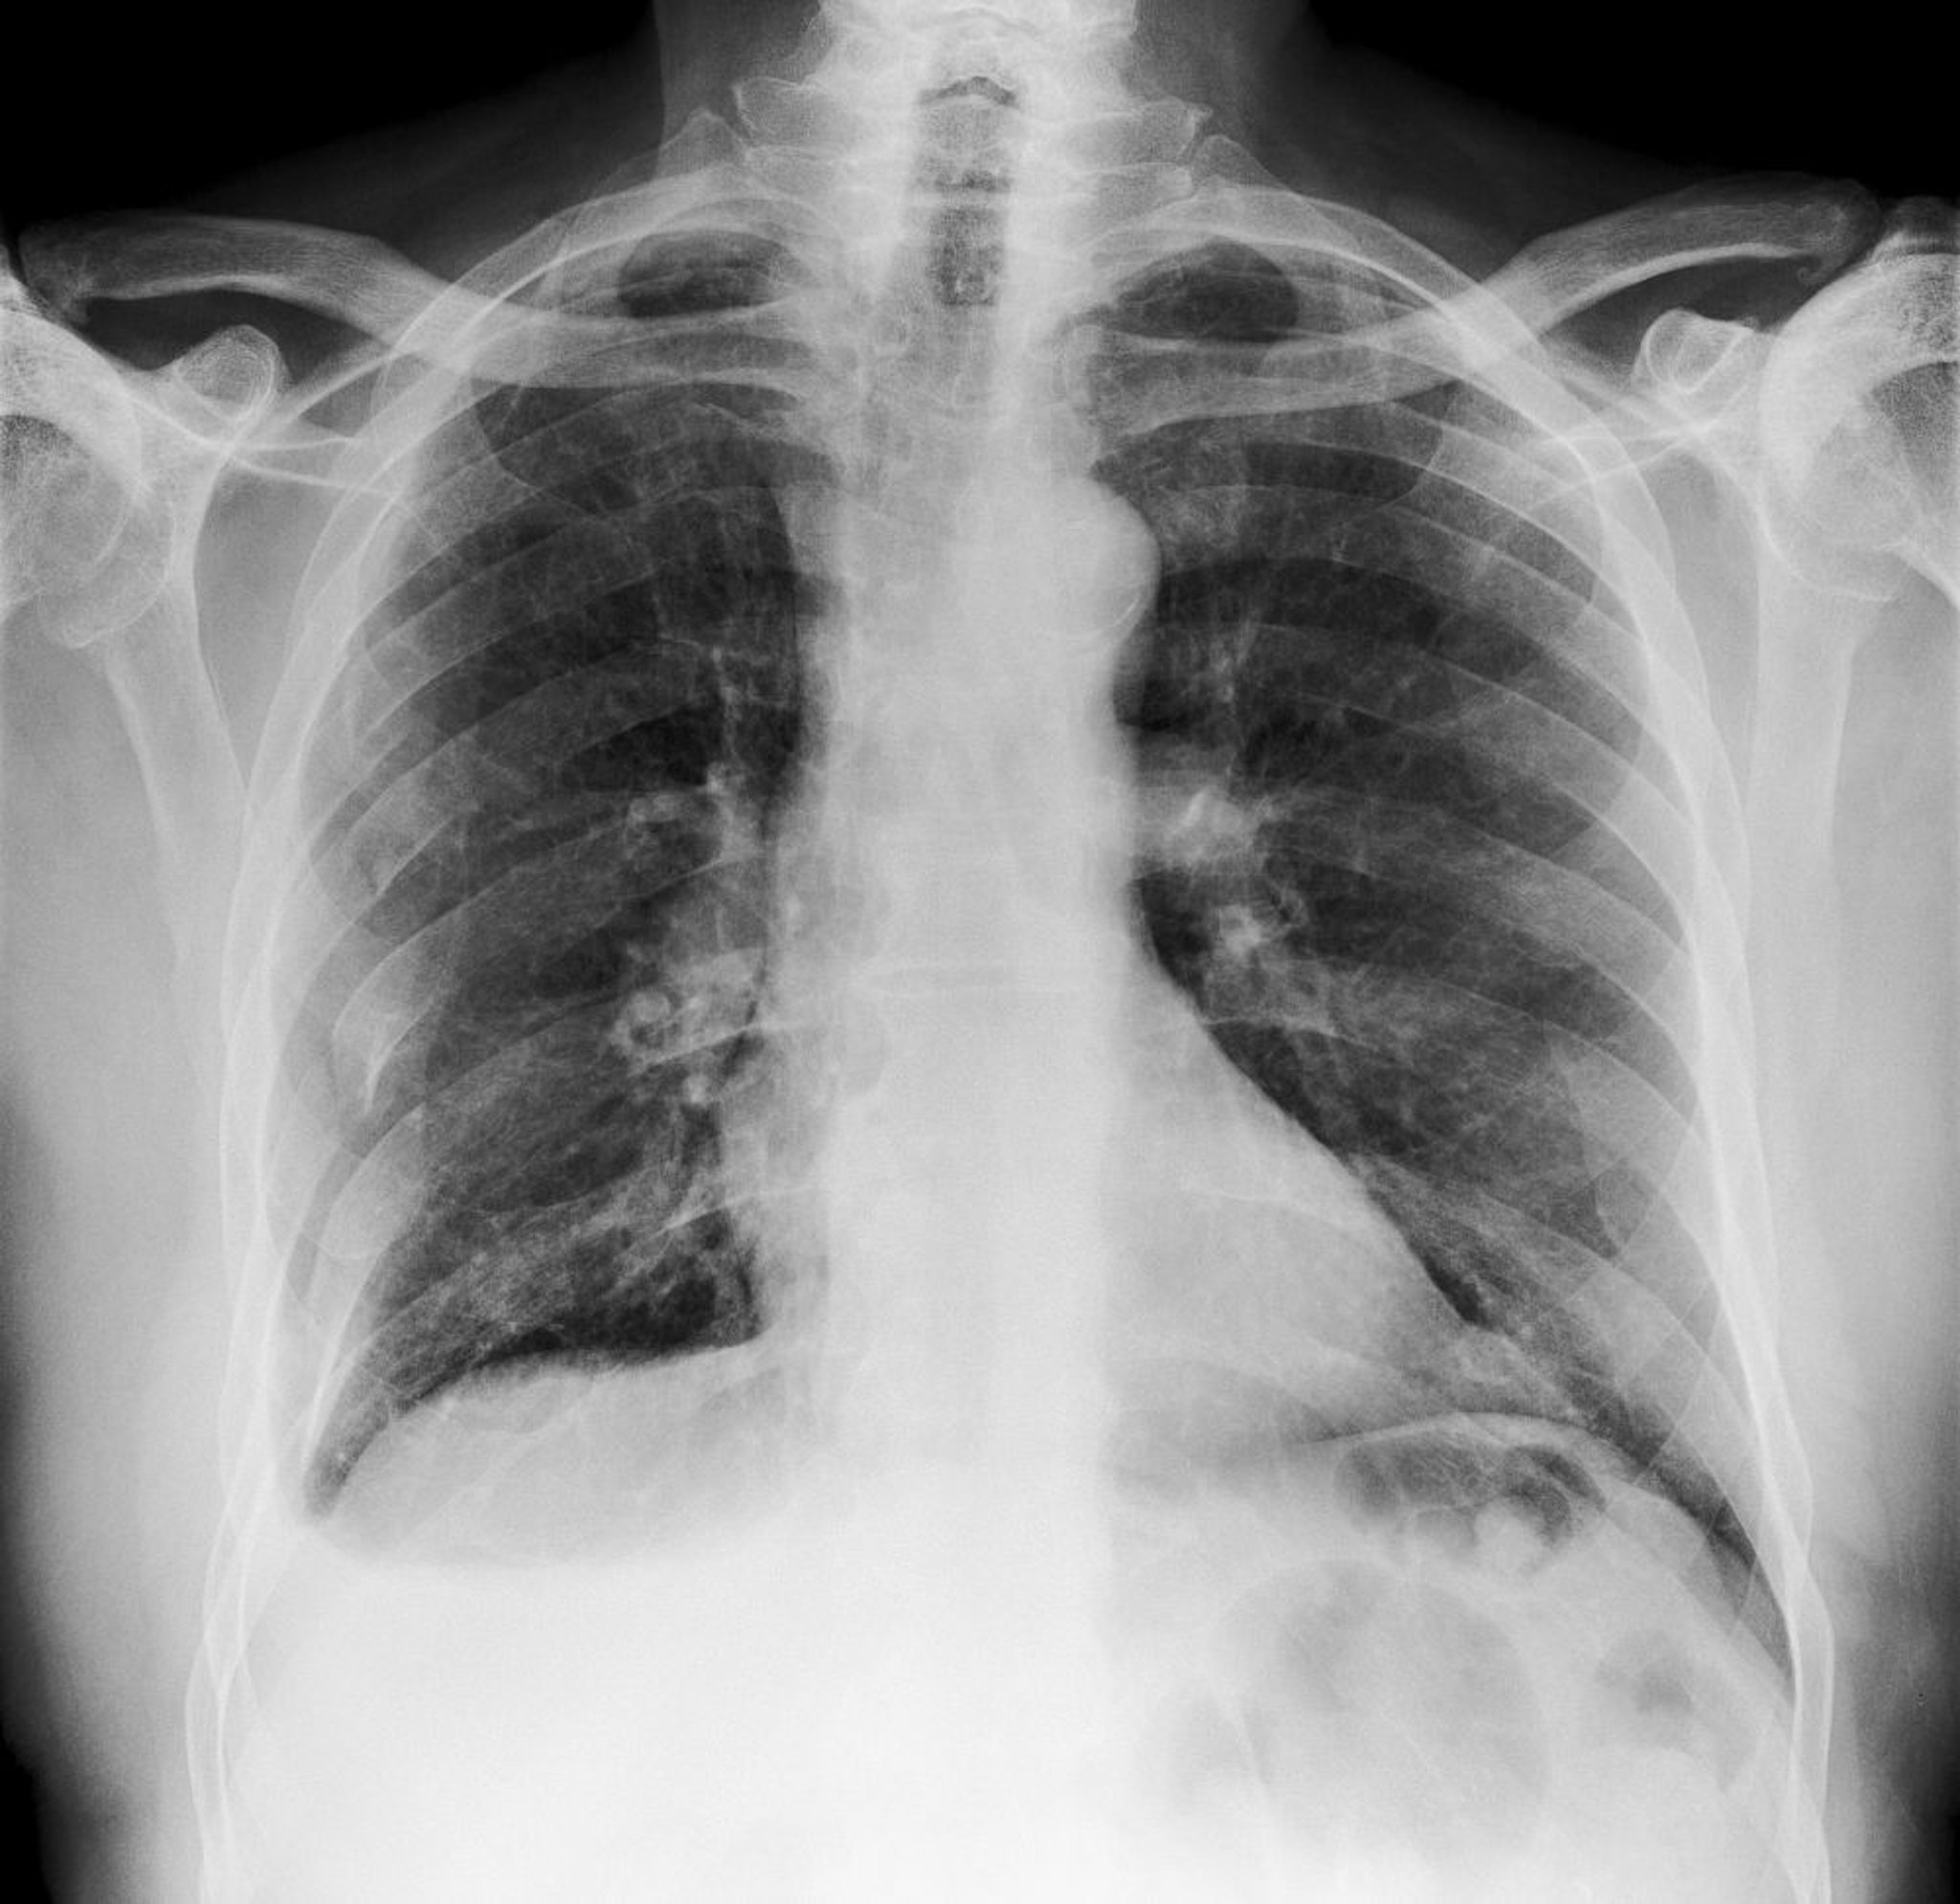

Esta radiografía torácica muestra múltiples fracturas en las costillas del lado derecho (vistas a la izquierda).